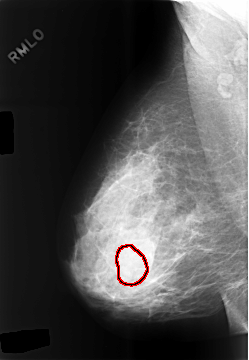

C_0478_1.RIGHT_MLO

FILE: C_0478_1.RIGHT_MLO.OVERLAY

TOTAL_ABNORMALITIES 1

ABNORMALITY 1

LESION_TYPE MASS SHAPE LOBULATED MARGINS CIRCUMSCRIBED

ASSESSMENT 4

SUBTLETY 2

PATHOLOGY BENIGN

TOTAL_OUTLINES 1

BOUNDARY